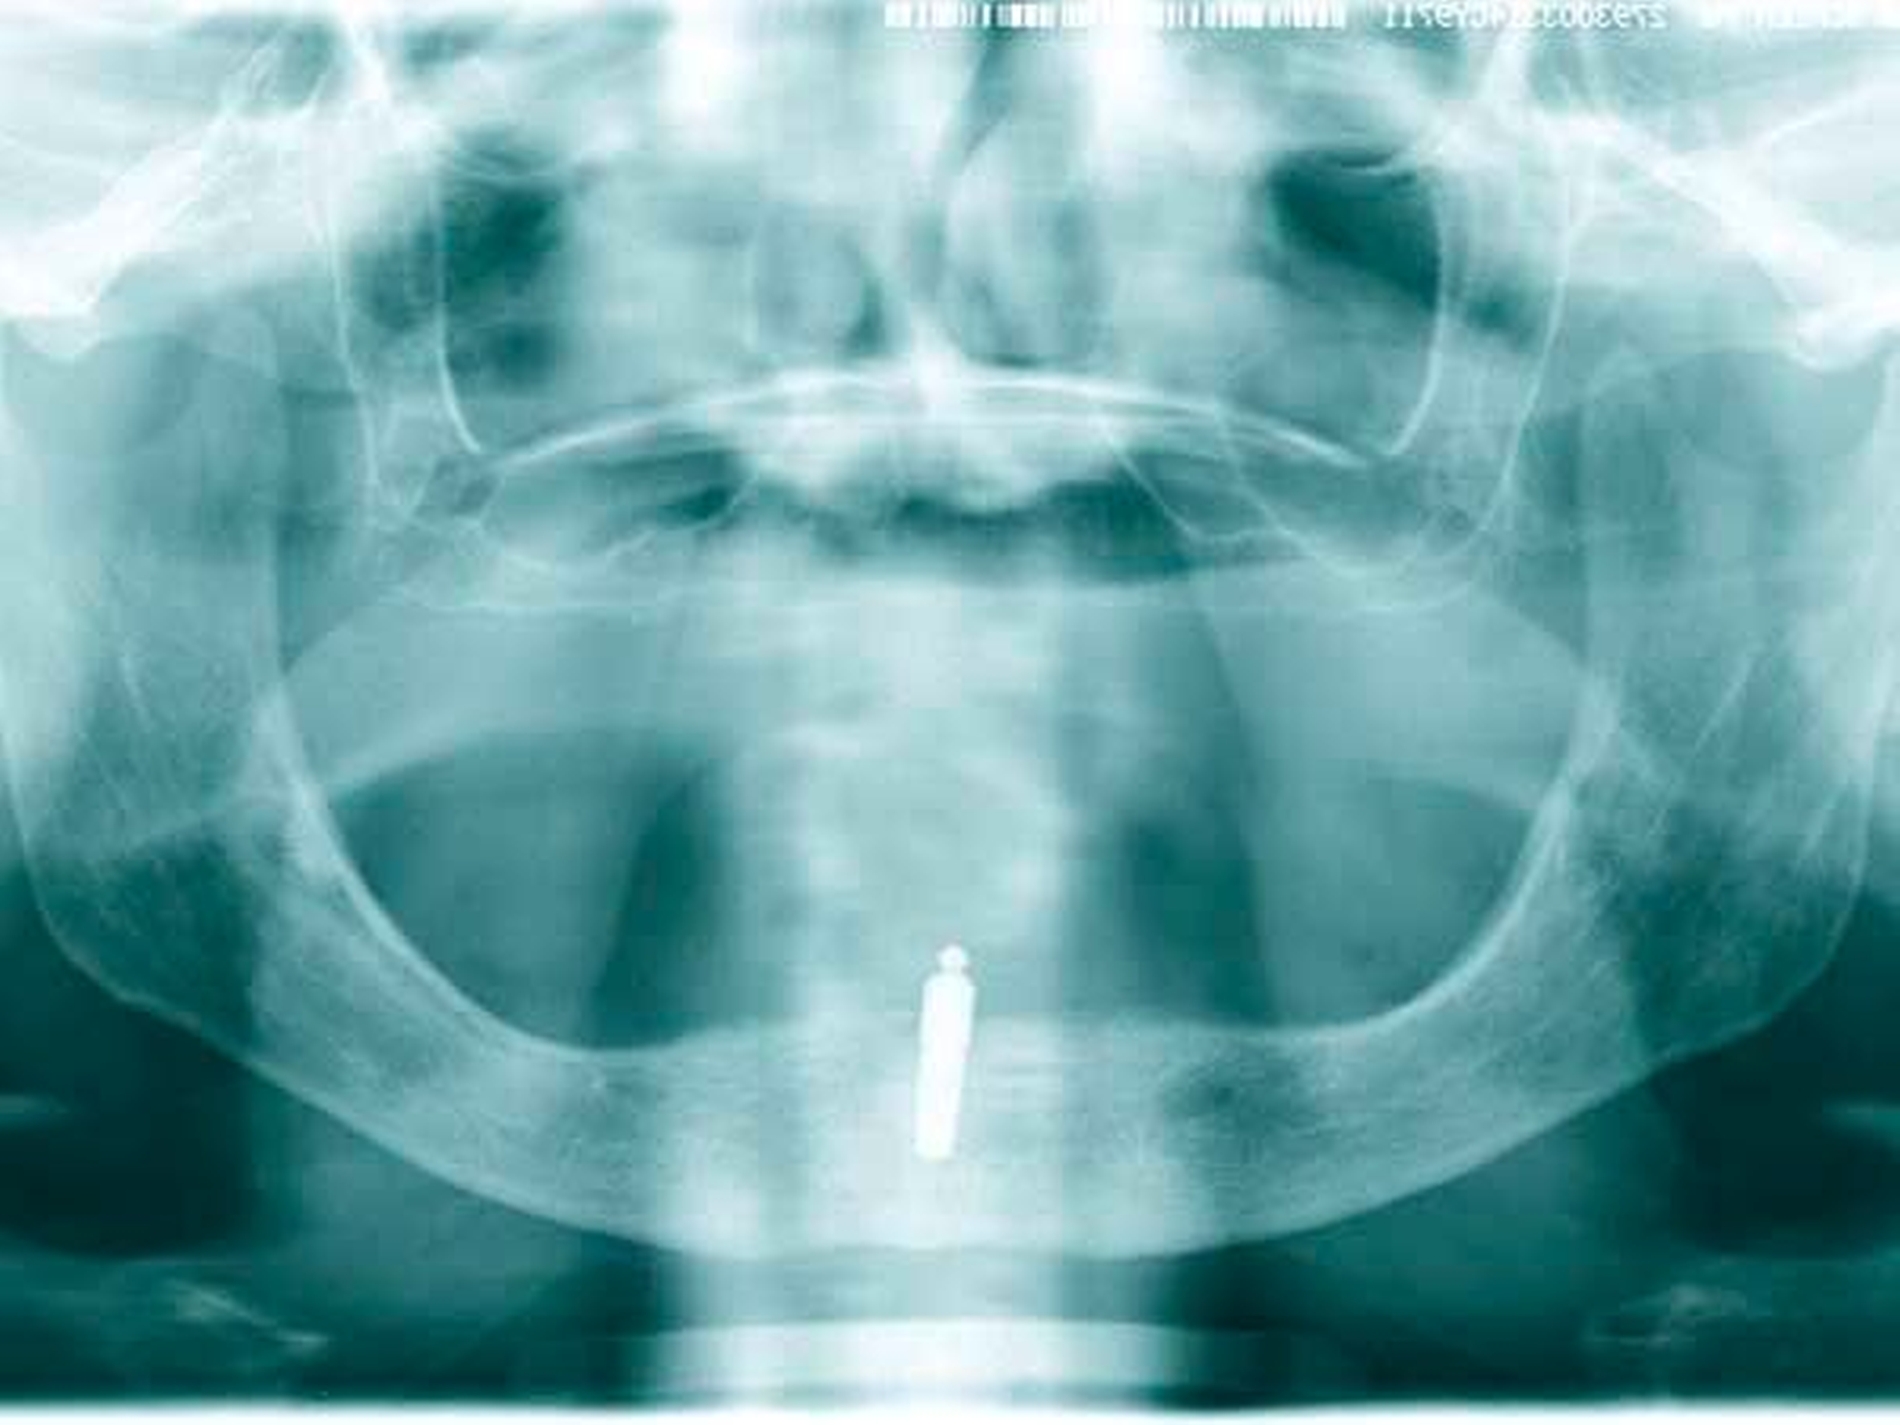

Konzept Einzelzahnimplantat: Das Konzept des mittigen Einzelimplantats im zahnlosen Unterkiefer wurde erstmals in den 1990er-Jahren von Cordioli et al. beschrieben [Cordioli G et al., 1997] (Abbildungen 1 bis 6).

Die Studie: In einer weltweit ersten multizentrischen randomisierten klinischen Studie wurde jetzt über einen Nachuntersuchungszeitraum von zwei Jahren der Einfluss des Belastungszeitpunkts auf das Versorgungskonzept des mittigen Einzelimplantats im zahnlosen Unterkiefer untersucht [Kern M et al., 2017].

Studiendesign: Hierzu wurden an neun Universitätszahnkliniken in Deutschland 158 zahnlose Patienten mit einem Implantat im Unterkiefer versorgt und entweder in die Sofortbelastungsgruppe (n = 81) oder in die Spätbelastungsgruppe (n = 77) randomisiert. In der Sofortbelastungsgruppe wurden die Implantate unmittelbar nach der Implantation mit einem Kugelkopfattachment versorgt. Die Implantate der Spätbelastungsgruppe heilten für drei Monate geschlossen ein und wurden am Tag der Freilegung ebenfalls mit einem Kugelkopfattachment versorgt (Abbildung 1).

Ergebnisse: Innerhalb der ersten drei Monate gingen neun Implantate (12,2 Prozent) der Sofortbelastungsgruppe und ein Implantat (1,5 Prozent) der Spätbelastungsgruppe verloren [Kern M et al., 2017]. Über einen Nachuntersuchungszeitraum von zwei Jahren ging kein weiteres Implantat verloren. Unabhängig vom Belastungszeitpunkt konnten bereits vier Monate nach Belastung der Implantate die Patientenzufriedenheit und die Kaueffektivität signifikant gesteigert werden [Passia N et al., 2017; Passia N et al., 2017/2] im Vergleich zur Ausgangssituation ohne Implantate mit konventioneller Totalprothese.